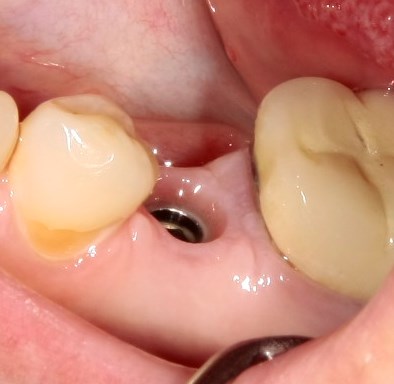

Немедленная имплантация — оптимальное решение в любой клинической ситуации